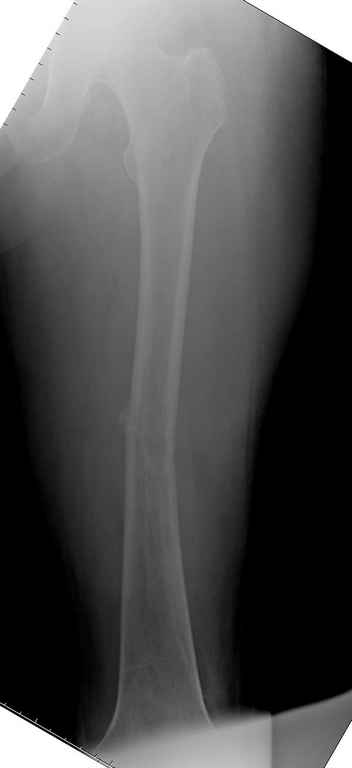

Здесь случай 66 летней пациентки со спонтанными болями в левой нижней конечности, обратилась в приемное, сделаны снимки бедра и КТ.

Патологический перелом бедра, конечность на вытяжении.

Известно, что многие из нас независимо от метода лечения и стадии первичной опухоли проводят интрамедуллярное штифтование при различных патологических состояниях бедра, включая патологические переломы.

С минимальным рассверливанием и ретроградным методом провели остеосинтез бедра 12 мм гвоздем. (17-20)

Кровопотеря во время операции меньше 100 мл.

Больная выписана, взятый во время рассверливания материал изучается.